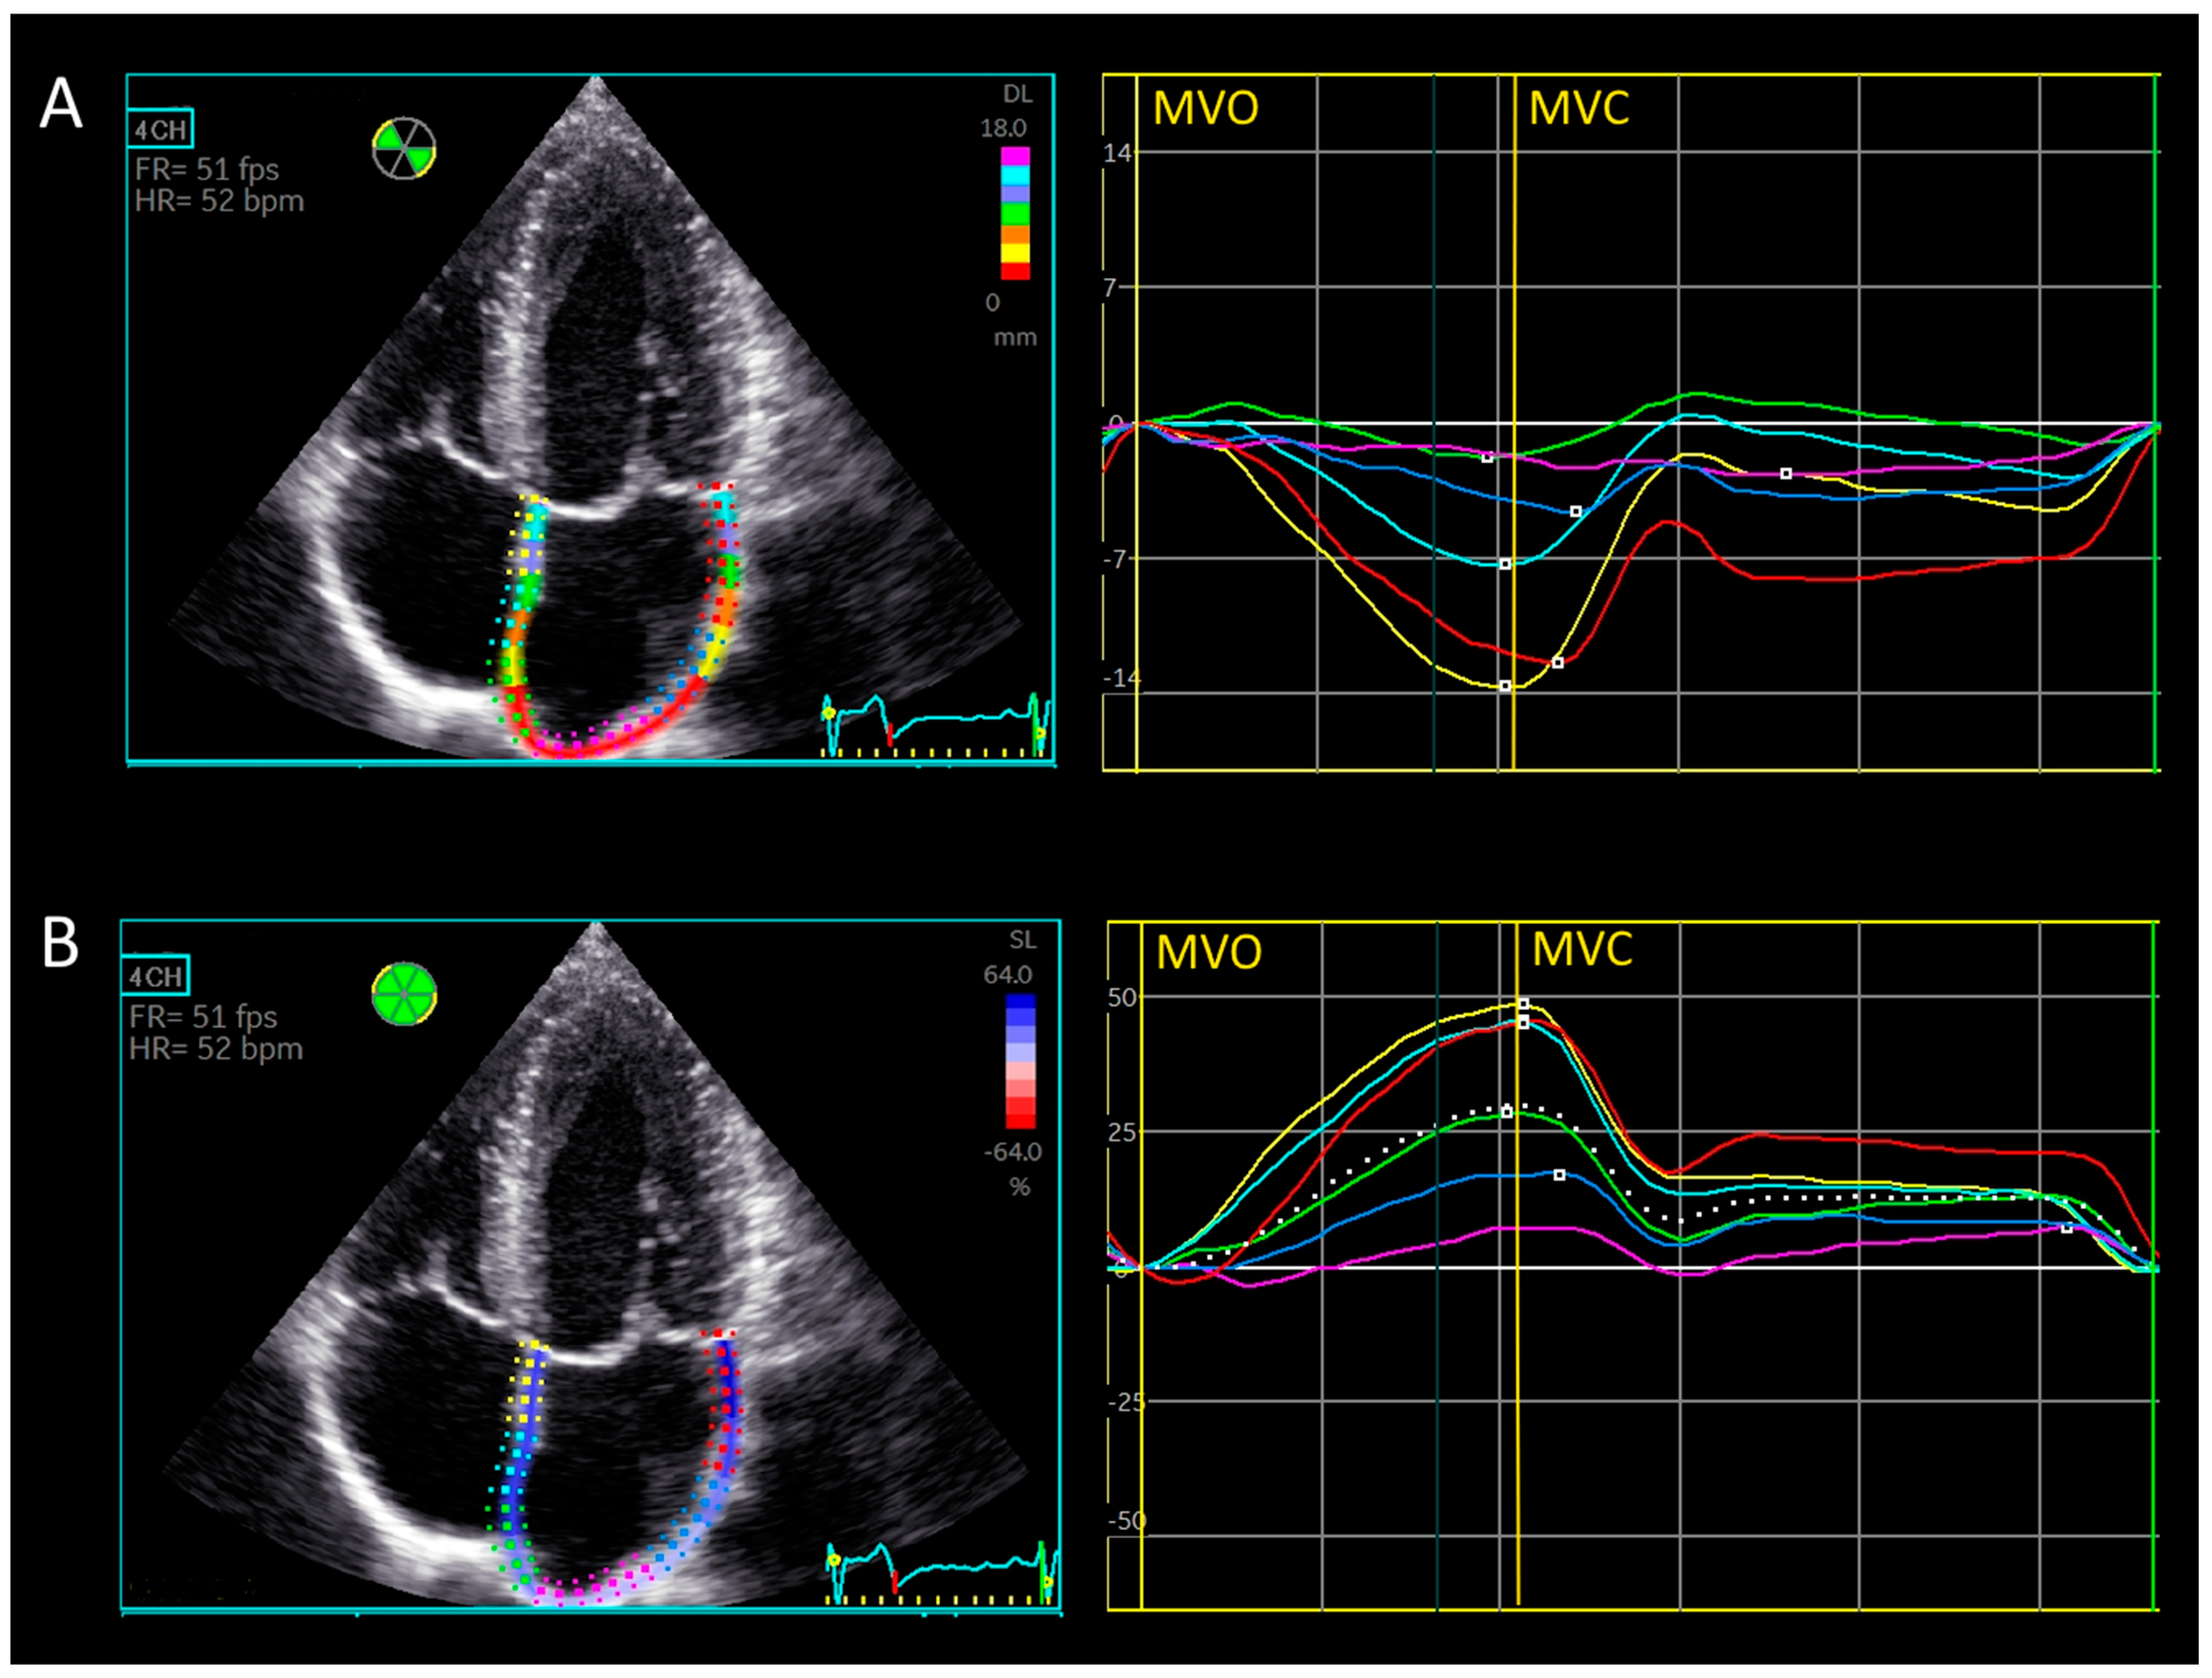

2.2.1. Automatic Biplane Method for Left Atrial Strain [15]

2.2.2. Manual Triplane Left Atrial Strain Assessment Using Ventricular-Dedicated 2D Strain Software

2.2.3. Left Atrial Walls and Segment Definitions for Regional Strain Calculation

2.2.4. Longitudinal Displacement

3.3. Longitudinal Displacement

3.4. Left Atrial Wall Motion Analysis